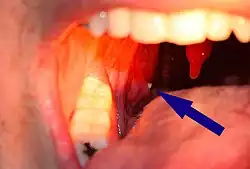

Tonsillolith, der Gaumenmandel anhaftend

Tonsillensteine (auch Mandelsteine oder Tonsillolithe) sind wenige Millimeter große Gebilde aus dem Rachenraum von weiß-gelblicher Farbe und von weicher bis fester Konsistenz, die einen unangenehmen Geruch aufweisen. Sie können in den Krypten der Gaumenmandeln (Tonsilla palatina) – oder seltener in der Zungenmandel (Tonsilla lingualis)[1] – entstehen und bestehen aus Speiseresten und abgestoßenen Zellen der Schleimhaut. Tonsillensteine verursachen in der Regel keine Symptome und sind nicht behandlungsbedürftig.[2] Größere Tonsillensteine können Halsschmerzen oder Schluckbeschwerden verursachen[2], wobei sich kleinere Tonsillensteine meist spontan lösen. Weiterhin können Tonsillensteine eine Ursache für Mundgeruch sein.[3]

An den Kryptenöffnungen sichtbare Tonsillensteine können fälschlicherweise mit Fibrinbelägen einer Mandelentzündung (Stippchen) verwechselt werden. Beim ausschließlichen Vorhandensein von Tonsillensteinen fehlt es jedoch an Entzündungszeichen wie Rötung, Schwellung oder Halsschmerzen.